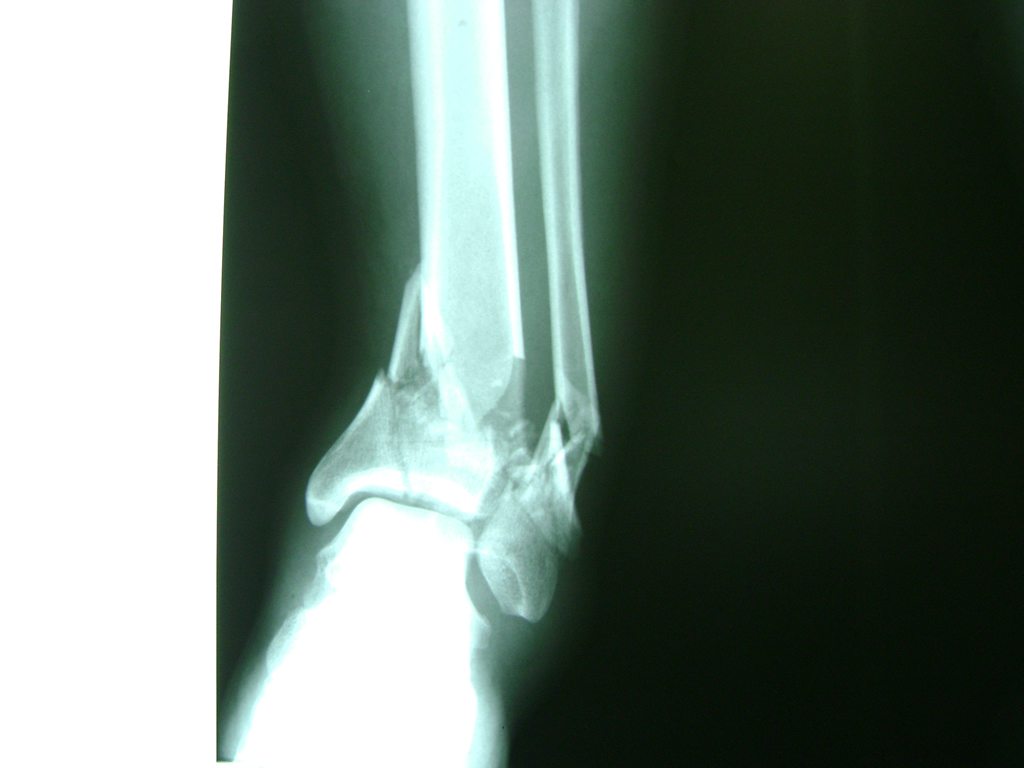

Una fractura de tobillo es la rotura de uno o más de los huesos del tobillo. Estas fracturas pueden ser:

Algunas fracturas de tobillo pueden requerir cirugía si:

- Los extremos de los huesos están desalineados entre sí (desplazados).

- Los tendones o ligamentos (tejidos que sujetan los músculos y los huesos entre sí) están rotos.